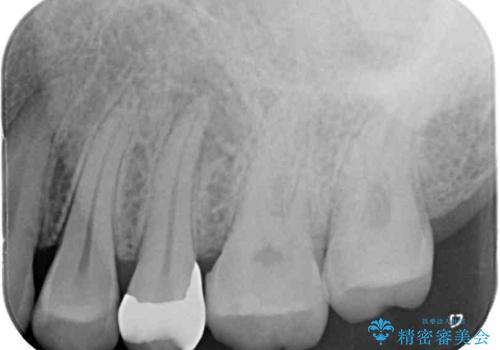

診査の結果、既に歯の神経は失活しており、レントゲンより根尖部に病変を認めました。

根管治療を行った奥歯は、再発防止や残された歯質を守るため、クラウンによる補綴治療が必要となります。

補綴後数ヶ月経過しレントゲンを撮影したところ、根尖周辺の病変が消退してきていることが確認できました。